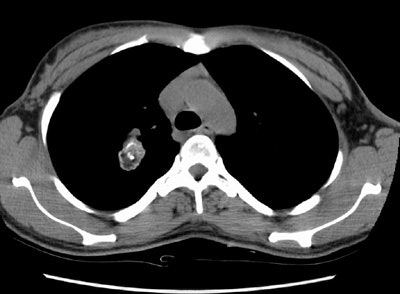

Pulmonary Hamartoma

The patient shown in the case below was referred for evaluation of a right upper lobe mass. The CT scan demonstrates a large mass in the right upper lobe that contained macroscopic fat consistent with a hamartoma. Lung windows demonstrated the lesion to be endobronchial and this was confirmed at surgical resection. (Click images to enlarge)